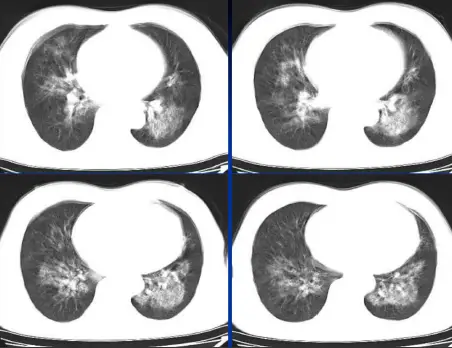

病例:男,44岁,咳嗽,咳血一周。3天前双侧膝关节疼痛,按风湿输水治疗时突然胸闷、气短。化验肾功能衰竭。高血压病3年。

病例:男,33岁,急性肾衰肺水肿。CT表现:①肺间质性肺水肿:两肺血管束增多、增粗,边缘模糊;②肺泡性肺水肿:两肺透光度减低,并见广泛性分布结节样、斑片样密度增高影及毛玻璃样影,边缘模糊,以两肺内、中带分布较明显,形成典型“蝶翼征”;③胸腔积液。

肾性肺水肿,主要是水钠潴留过多、贫血(肾衰导致促红细胞生成素降低)致血浆胶体渗透压降低,临床症状主要表现为少尿、高血压及心力衰竭。肾性肺水肿肺纹理普遍增粗,血管蒂增宽。肺实变阴影中央分布较多。

②肺泡性肺水肿及间质性肺水同时存在,而以肺泡性肺水肿为主;

③胸腔积液。又称尿毒症肺。